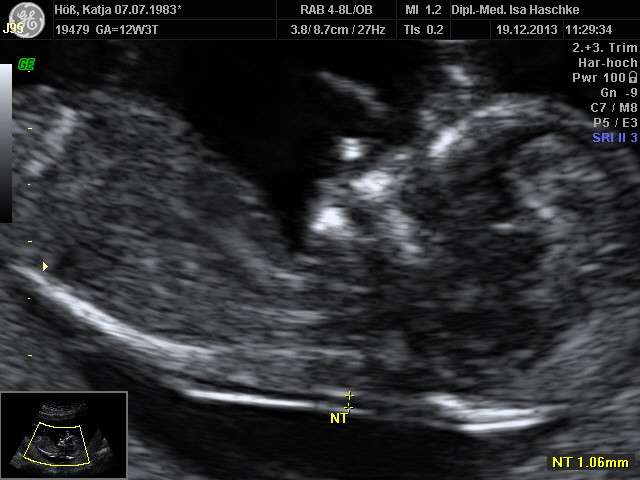

Schwangerschaftswoche 13

Nach unserer Zustimmung und Einverstandnis konnte nun die Nackenfaltenmessung des ungeborenen gemacht werden, am 19.12.2013 wurde diese durchgeführt. Der Befund ist positiv ausgefallen, zu 0,0083 % konnte eine Fehlbildung ausgeschlossen werden, worüber wir sehr glücklich sind.